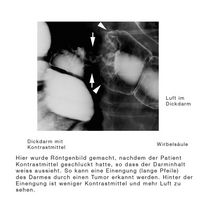

Wenn die Darmöffnung durch den Tumor schon so weit zugewachsen ist, dass man mit der Kamera nicht mehr durchkommt, wird der Darm mit Kontrastmittel gefüllt, und die Kontur der Darmwand mit Hilfe eines Röntgenbildes dargestellt.